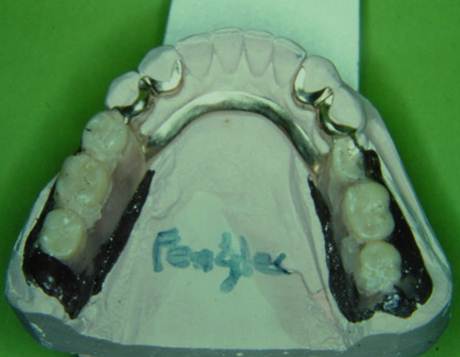

噛み合わせの器械につけて、ワックスで形を作り、診断をしたり、仮の歯を作ります。

リーゲルのレバーがかかる部分です。

そして、完成です。

リーゲルレバーの形、シングルロック、ダブルロックの設計、シュレーダーゲシーベの位置、回転軸の深さなど、大変細かいところではありますが、Körber教授から直接学んだ方法のままに現在も行われております。